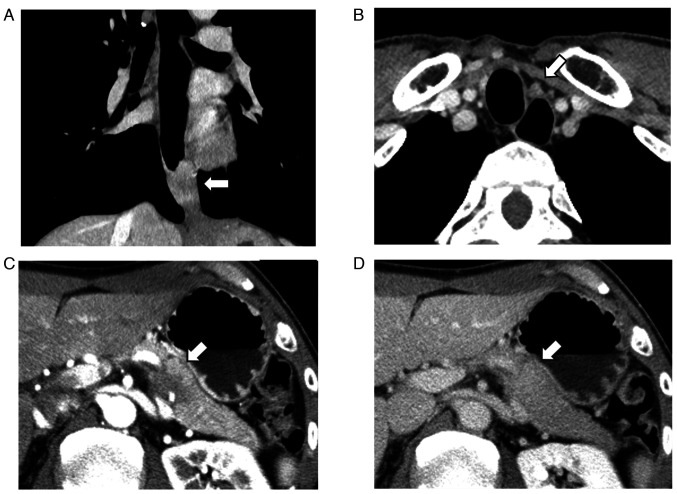

胰腺转移的频率有限,而食道鳞状细胞癌转移的频率则更加有限。有报道称,一些患者的这类转移性病灶可进行根治性切除,但这些手术能给患者带来的生存益处尚未明确确定。本研究中的患者是一名 54 岁的男性,被诊断为下胸段食管癌。计算机断层扫描显示,胰腺尾部有一个 2 厘米的肿瘤。由于没有发现其他明显的远端转移灶,患者同时接受了外科手术,切除了食管鳞状细胞癌和胰腺转移灶。组织病理学检查证实,两份标本均为鳞状细胞癌。自切除术后,患者已痊愈 9 个月。对迄今为止所有相关病例的文献回顾也表明,所有出现胰腺转移的食管癌患者的原发肿瘤部位都是下胸段食管。完全同时切除食管鳞状细胞癌和胰腺单发转移瘤是有益的,可能会产生良好的疗效。然而,由于相应的报告数量较少,还需要进一步的研究来证实手术的益处。

The frequency of metastasis to the pancreas is limited, and the frequency of metastasis of a squamous cell carcinoma of the esophagus is limited even further. The curative resection of this type of metastatic lesion has been reported for some patients; however, the survival benefit that can be attributed to these procedures has not yet been clearly determined. The patient examined in the present study was a 54-year-old man who was diagnosed with a lower thoracic esophageal cancer. Computed tomography revealed a 2-cm tumor at the tail of the pancreas. Since no other obvious distal metastases were observed, the patient underwent simultaneous surgical procedures, excising the esophageal squamous cell carcinoma and the pancreatic metastasis. A histopathological examination confirmed squamous cell carcinoma in both specimens. The patient has been free of disease for 9 months since the resection. A literature review of all relevant cases to date also demonstrated that the primary tumor site in all cases of patients with esophageal cancer presenting with metastasis to the pancreas was the lower thoracic esophagus. Complete simultaneous resections of esophageal squamous cell carcinoma and a solitary metastasis to the pancreas is beneficial and may produce favorable outcomes. However, due to the reduced number of corresponding reports, further studies are required for the confirmation of the benefits of surgery.